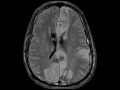

Intracranial Vasospasm

These images demonstrate diffuse subarachnoid hemorrhage, large intraventricular hemorrhage, and small bilateral subdural hemorrhages as evidenced by decreased signal on the susceptibility weighted images. There are multifocal areas of restricted diffusion and associated mildly expansile T2 FLAIR hyperintensity throughout the supratentorial brain, cerebellum, and brainstem. Axial 3D time of flight imaging of the circle of willis with multiplanar maximum intensity projection images shows multifocal areas of narrowing involving the bilateral internal carotid artery termini, proximal M1 segments, proximal A2 segments, distal right V4 segment, and right P2 segment. Findings are compatible with vasospasm and extensive associated ischemic infarcts secondary to diffuse subarachnoid hemorrhage from a ruptured aneurysm found in the left V4 segment which was status post coiling.